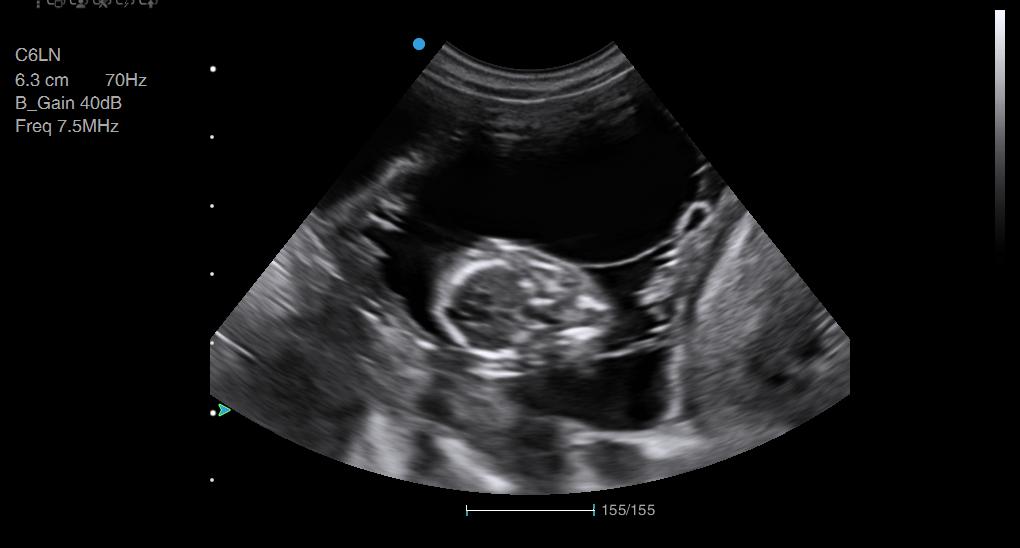

Rosey Dachshund Ultrasound Conisbrough Animal Ultrasound Association Dachshund Ultrasound Take your dachshund to the vet for a blood test or ultrasound if you suspect she is pregnant. During week 4, visit the vet once more to confirm the pregnancy through ultrasound examination. The spine and the eyes start to develop, and their faces begin to shape up. The best way to determine if your dachshund is pregnant is with. Dachshund Ultrasound.

Rosey Dachshund Ultrasound Conisbrough Animal Ultrasound Association Dachshund Ultrasound Around two to three weeks after. Your vet can perform an ultrasound to confirm the pregnancy and check the health of the embryos. At this stage, the fetuses are about the size of a. You might notice that your dog’s nipples are slightly enlarged. Ultrasound of a dachshund at approximately 33 days gestation. During week 4, visit the vet once. Dachshund Ultrasound.